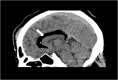

Figure 1

Brain CT—sagittal plane, white arrow shows a large, well-defined low-density lesion involving the genu and body of the corpus callosum.